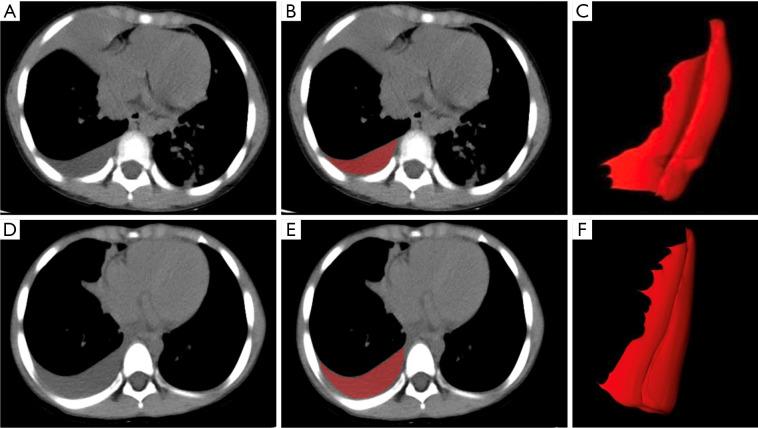

Bacterial pathogens and are the two main pathogens that cause community-acquired pneumonia complicated with pleural effusion (PE) in children, it is important to accurately differentiate between these two types of effusions. The aim of this study was to explore the feasibility and value of a radiomics approach based on non-contrast chest computed tomography (CT) scans in the differentiation of bacterial pneumonia PE (BPPE) and parapneumonic effusion (MPPE) in children.

The clinical and CT imaging data of hospitalized children with PE detected by chest CT scans from December 2020 to December 2023 were retrospectively collected. A total of 167 cases of BPPE and 368 cases of MPPE were included, and all cases were randomly divided into a training set and a test set in the ratio of 7:3. The region of interest (ROI) was manually segmented in images of non-contrast chest CT scans to extract radiomics features. The optimal radiomics features were screened using Select K Best, max-relevance and min-redundancy (mRMR), least absolute shrinkage and selection operator (LASSO). Logistic regression (LR) was selected to construct the radiomics model. The receiver operating characteristic (ROC) curves were plotted, and the area under the curve (AUC), 95% confidence interval (CI), sensitivity, specificity, and accuracy were calculated to evaluate the model performance.

回顾性收集2020年12月至2023年12月期间因胸部CT扫描检测出患有PE的住院儿童的临床和CT影像数据。共纳入167例BPPE和368例MPPE病例,所有病例按7:3的比例随机分为训练集和测试集。在非增强胸部CT扫描图像中手动分割感兴趣区域(ROI)以提取放射组学特征。使用最佳子集选择(Select K Best)、最大相关最小冗余(mRMR)、最小绝对收缩和选择算子(LASSO)筛选最佳放射组学特征。选择逻辑回归(LR)构建放射组学模型。绘制受试者工作特征(ROC)曲线,并计算曲线下面积(AUC)、95%置信区间(CI)、敏感性、特异性和准确性以评估模型性能。